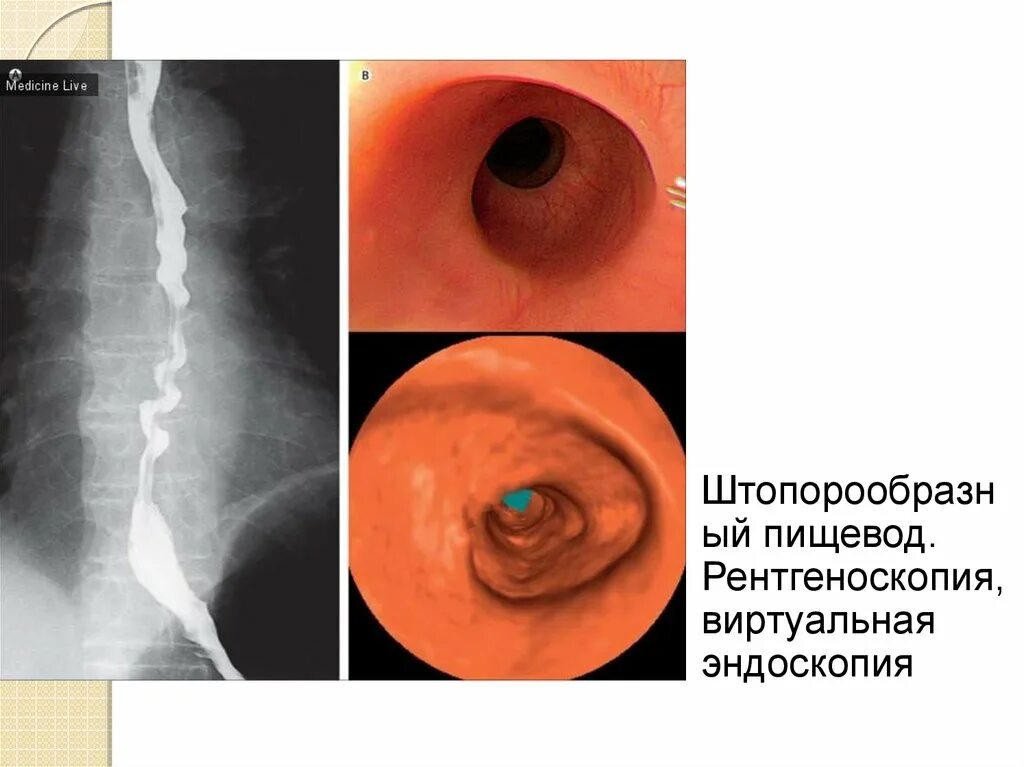

Диффузный эзофагоспазм